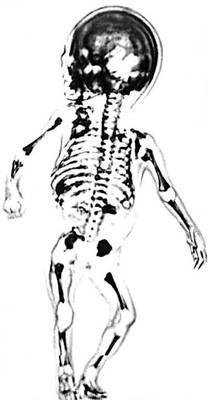

Большая Советская Энциклопедия (УЛ) - i010-001-273797225.jpg

Рис. 7. Звуковое изображение человеческого плода возраста 17 недель, полученное с помощью ультразвука частотой 5 Мгц .